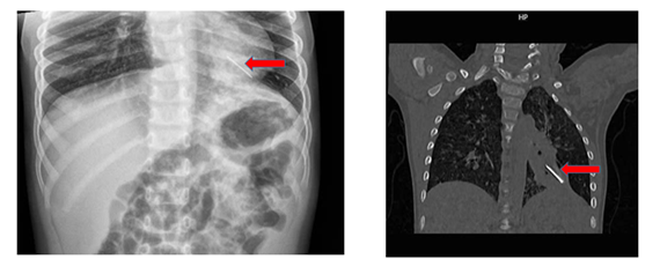

Hình ảnh chụp Xquang và đoạn kẽm nhung sau khi được bác sĩ phẫu thuật lấy ra ngoài

Tại bệnh viện, chỉ số SpO2 còn 90%, nhịp thở nhanh, co kéo cơ hô hấp, phế âm bên trái giảm nhẹ. Kết quả chụp X-quang và CT scan ngực ghi nhận có dị vật cản quang tại thùy dưới phổi trái.